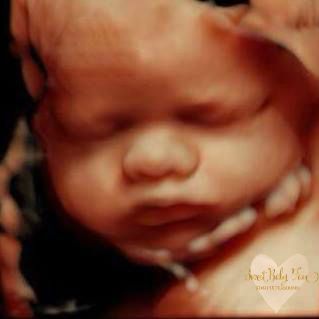

3D/4D/5D Ultrasound Gallery

Take a peek at our Photo Gallery. All of our 2D, 3D, 4D, HD elective ultrasound images are truly ours. They come directly off our machine from our highly trained staff. We can start getting great 3D/4D images as early as 10 weeks!